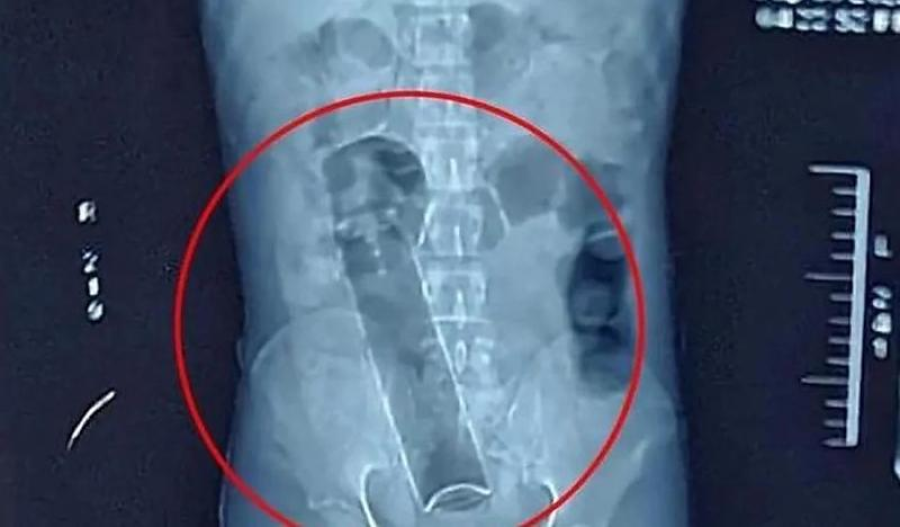

Um caso inusitado e delicado mobilizou equipes médicas do Hospital João Paulo II, em Porto Velho (RO), na quarta-feira (12). Um homem — que não teve a identidade divulgada — procurou a unidade de saúde com fortes dores abdominais após ter introduzido um frasco de desodorante no reto e não conseguir retirá-lo.

De acordo com informações apuradas por sites locais, o paciente relatou que tentou remover o frasco por conta própria, mas a dor intensa o obrigou a buscar atendimento de urgência. Após avaliação clínica e realização de exames, os profissionais constataram que o objeto estava preso e poderia causar complicações internas.

Diante da situação, a equipe médica levou o homem ao centro cirúrgico para realizar um procedimento destinado à retirada segura do corpo estranho, evitando danos mais graves ao intestino.